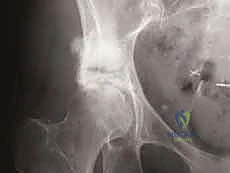

Our patient today presents with a supra-acetabular lesion, which falls under Harrington's Class I classification. This means the tumor is confined to the supra-acetabular region, sparing the medial wall and, critically, the ipsilateral femoral head. If the femoral head were involved, this extra-articular approach would be contraindicated, and we'd be looking at a total hip replacement.

- Plain Radiographs: We always start with plain AP and lateral radiographs of the pelvis and hip. These provide our initial assessment of the lesion's lytic or blastic nature and its general extent.